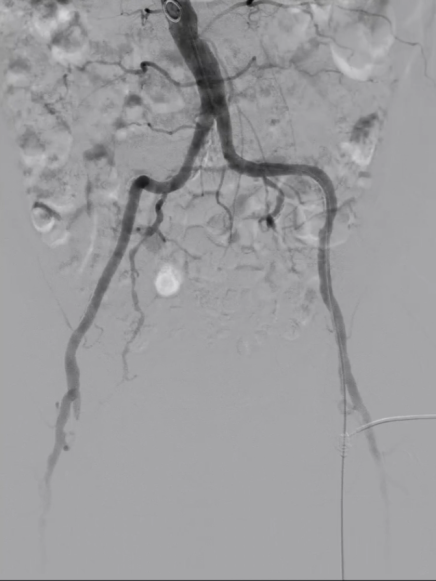

5

管腔准备与支架植入

预扩张:使用球囊扩张病变段,造影提示长段限流性夹层,需支架覆盖

治疗模式:因股腘动脉直径<4.5mm,选择DCB(药物涂层球囊)+BMS(裸金属支架)联合方案;

支架选择:在DCB扩张导管进行管腔准备后,植入2枚5mm INNOVA支架,其优势在于尾端定位精准,尤其适合累及开口或分叉的病变。